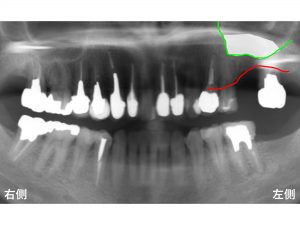

わかりやすいように骨吸収の状態を線でかいて見ます。

以下の青線が骨吸収する前の元々の骨の位置です。

現在の骨吸収した状態が以下の赤線です。

そして緑線が上顎洞の一番下の部分です。

この3つの線を組み合わせたのが以下です。

現在のように骨吸収している場合には、

インプラント治療が困難となります。

これではインプラントが長持ちするはずがありません。

そこで上顎洞の空洞の中に骨を増大させる治療が行われます。